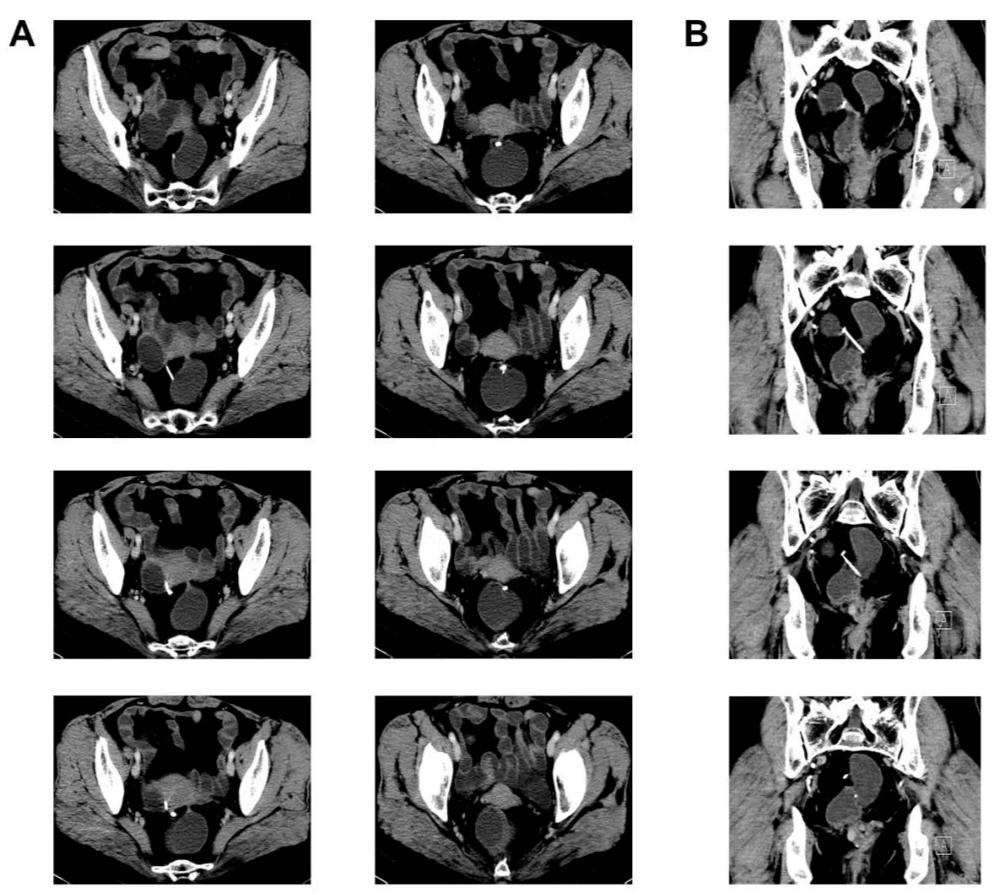

3.术前辅助检查

图1

图2

腹腔镜探查:子宫后位,萎缩;直肠前壁、子宫后壁及双侧子宫骶韧带致密粘连(刚进腹的时候连环的“影子”都看不到。

好在准备充分,结合术前的CT片及术中情况,以超声刀、剪刀逐渐分离开肠管与子宫后壁之粘连后,我们发现了肠子表面有一小片白色异物,没错,就是它了!

经过耐心的分离,“T”型环终于暴露出来了:原来它其中的一端短臂暴露在直肠表面,而长臂及另一端短臂全部扎入直肠前壁内。我们用抓钳夹住节育环后,以最小损伤肠管的方式将它从肠子里“揪”了出来,并将肠子进行了修补。